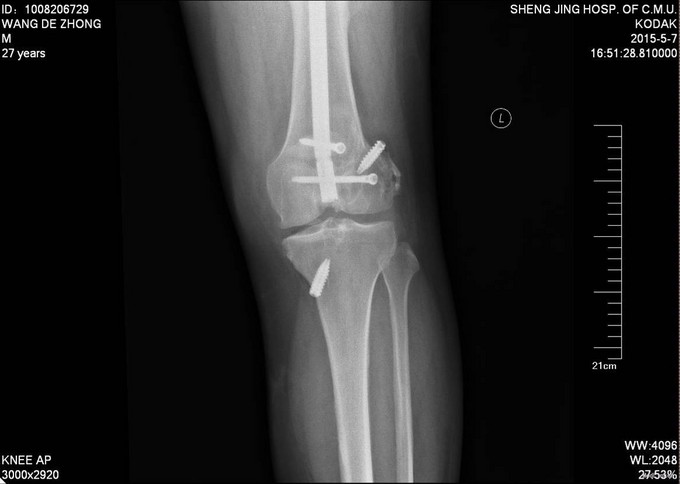

主诉:外伤后膝关节疼痛、活动受限8小时 患者8小时前打架被人钝器砸到膝关节后出现左下肢疼痛、活动受限、不能行走,受伤后意识清醒,略有头晕头迷。受伤后于我院急诊就诊,完善相关检查后以“髌骨骨折”为诊断收入院。患者目前一般状态可,无发热寒战,无恶心呕吐,受伤以来饮水未进食,未排气大便,小便如常。

专科查体:患者平车推入病房,左膝关节肿胀明显,活动障碍,左足足背动脉可触及,脚趾活动好,皮肤感觉无麻木。

诊断:左髌骨骨折 患者入院后见患肢肿胀明显,给予患肢抬高位,冷敷,甘露醇消肿等对症治疗,带患肢出现褶皱试验阳性后,全麻下行左髌骨骨折切开复位张力带内固定术,术后患者肿胀明显,给予抗炎,消肿,冷敷,患肢抬高等对症治疗。患者每天换药观察切口愈合情况,无红肿及渗出,待伤口14天后予以拆线治疗,予以出院,给予康复处方。